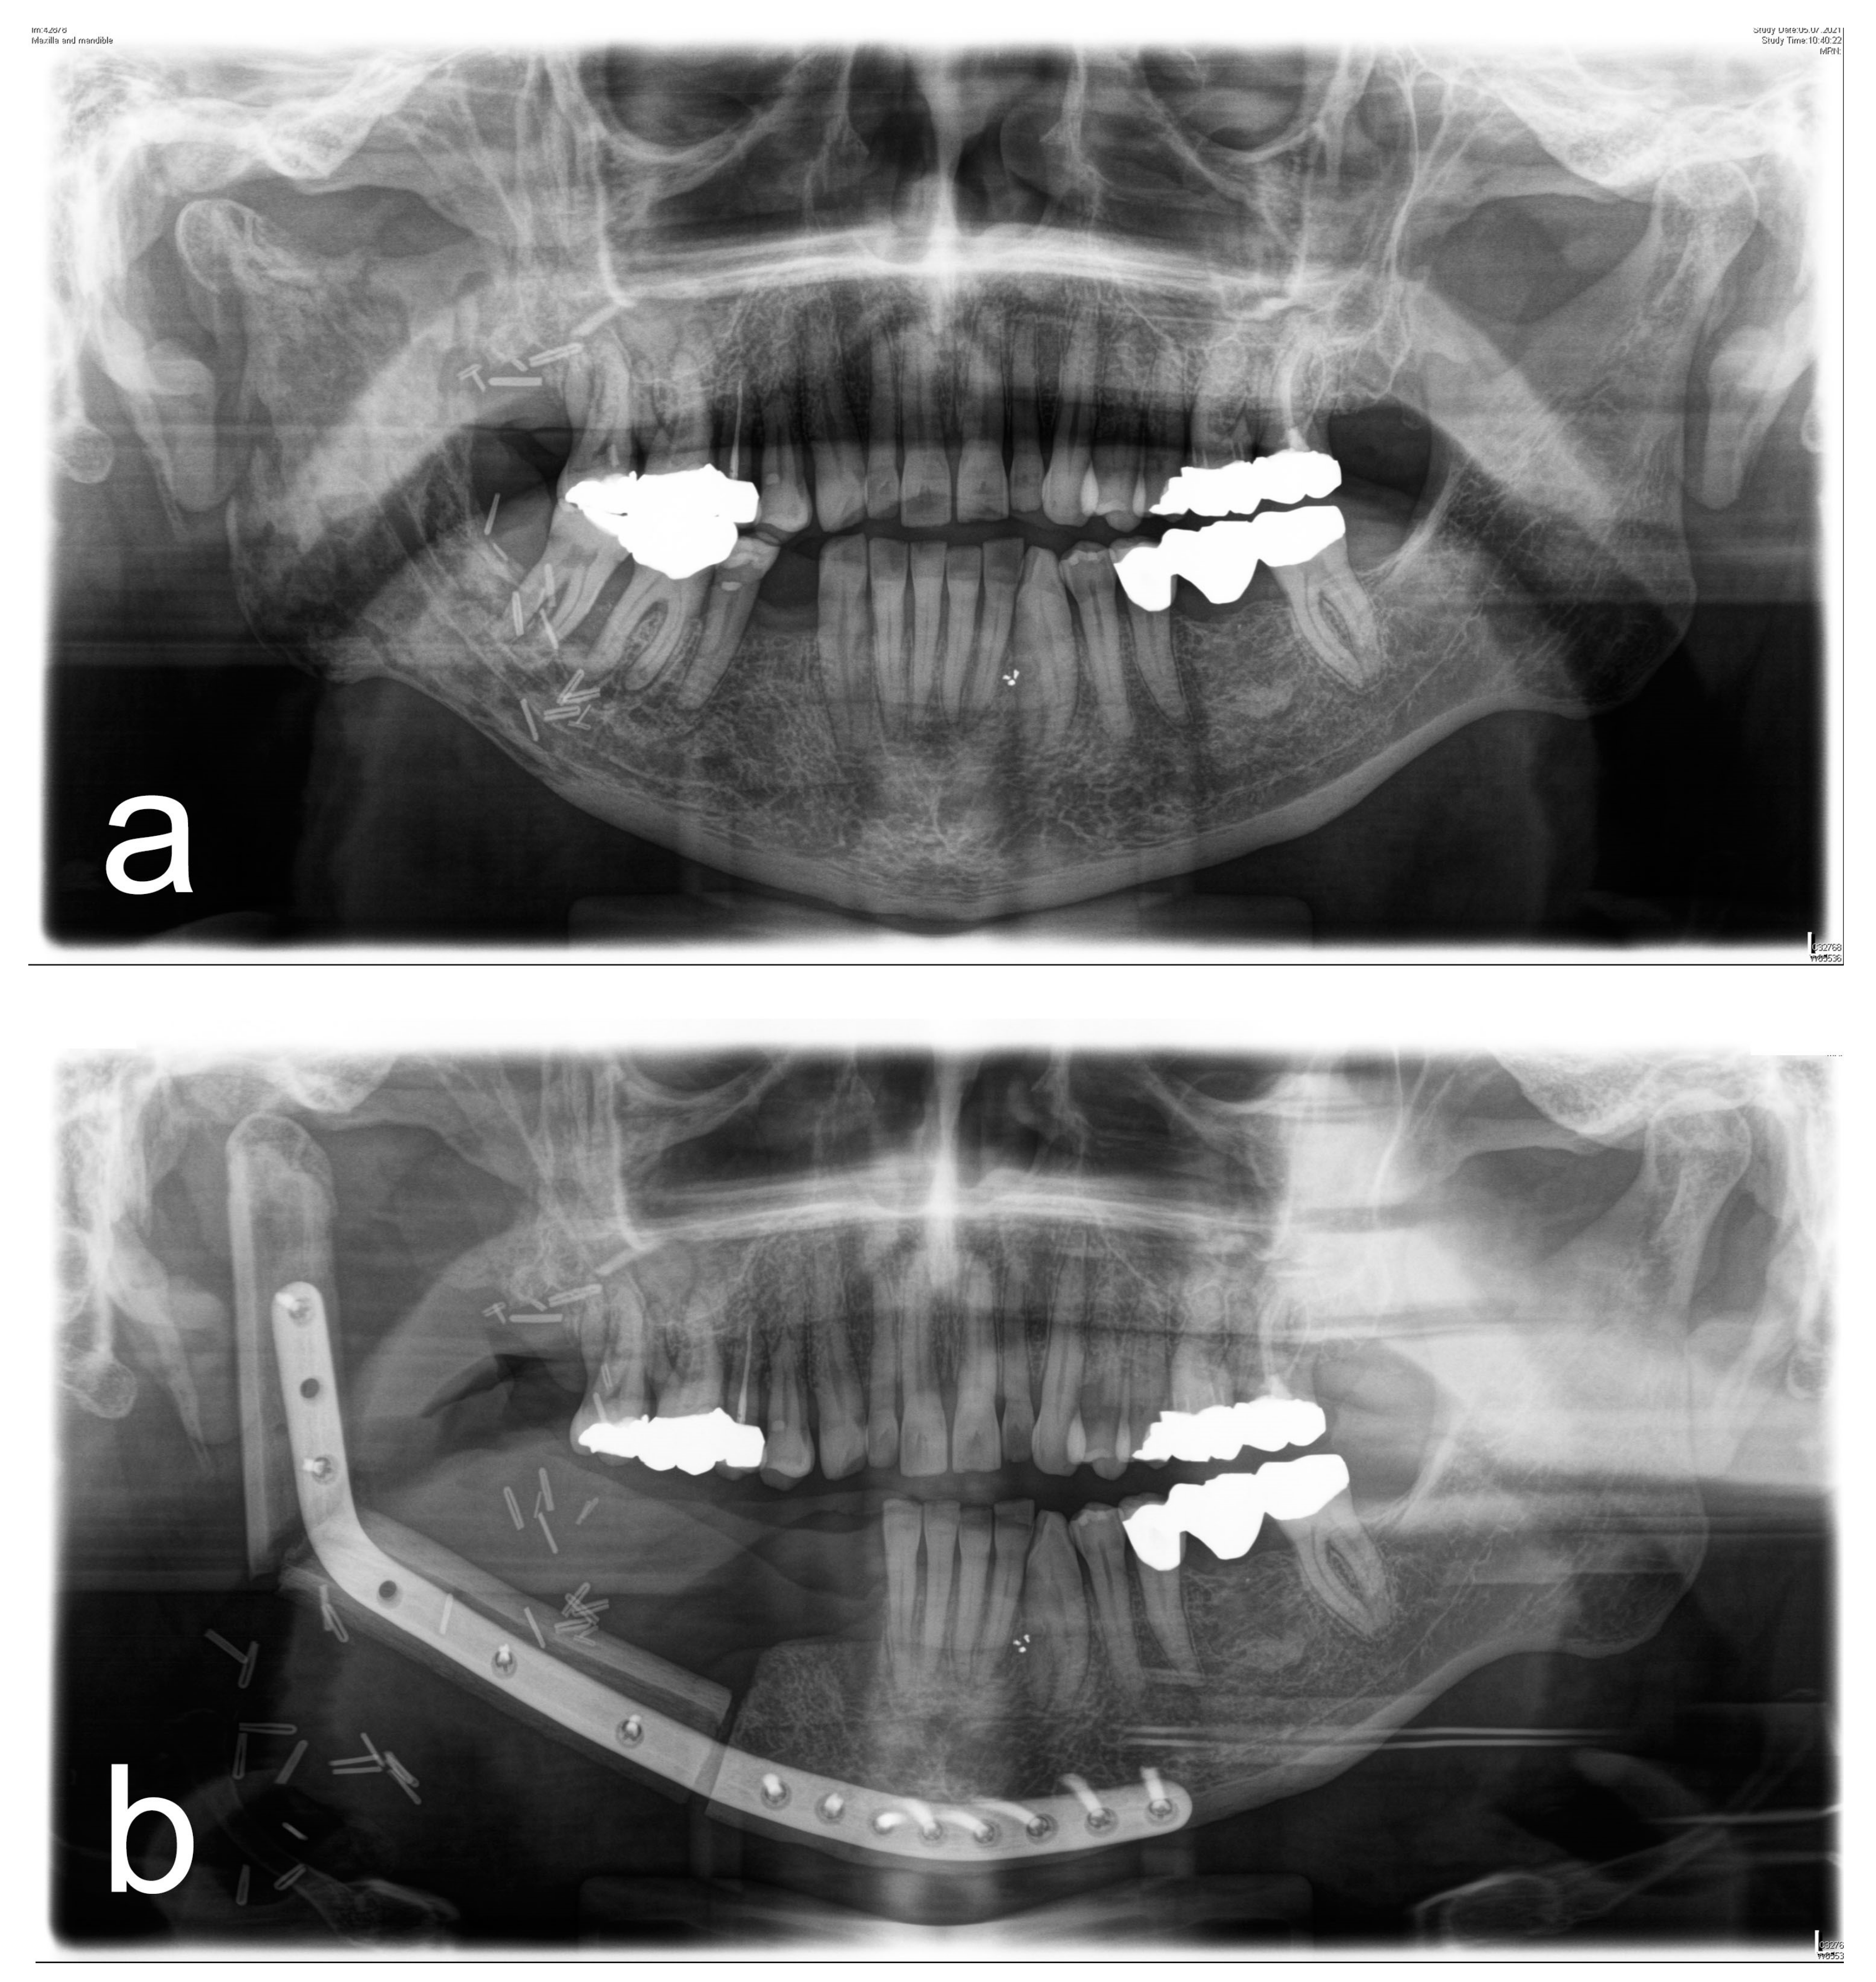

Figure 1, Figure 2, Figure 3 and Figure 4 illustrate two cases of advanced mandibular resection with severe hard and soft tissue injury followed by reconstruction using a vascularized fibula flap. This graft allows reconstruction of bone and soft tissue, the latter of which can be used to replace extraoral skin (Figure 2) or intraoral mucosa (Figure 4).

Figure 1. (a) Panoramic X-ray of a patient with extensive ORN of the mandible. (b) Postoperative panoramic X-ray of the same patient after ablative and reconstructive surgical therapy of ORN using a vascularized 2-segment fibula flap with intraoral soft-tissue transfer and patient-specific implant.